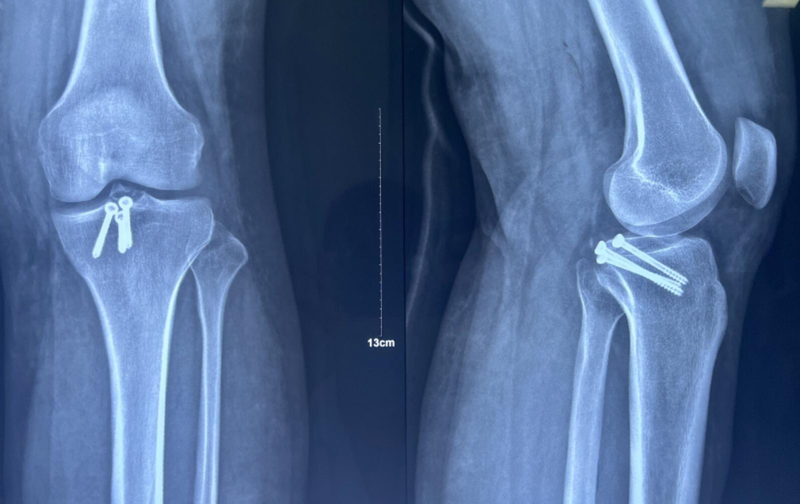

诊断:左胫骨平台后柱骨折,后交叉韧带撕脱骨折,左踝关节pilon骨折3型。

图7 前交叉韧带撕脱骨折与平台后柱骨折